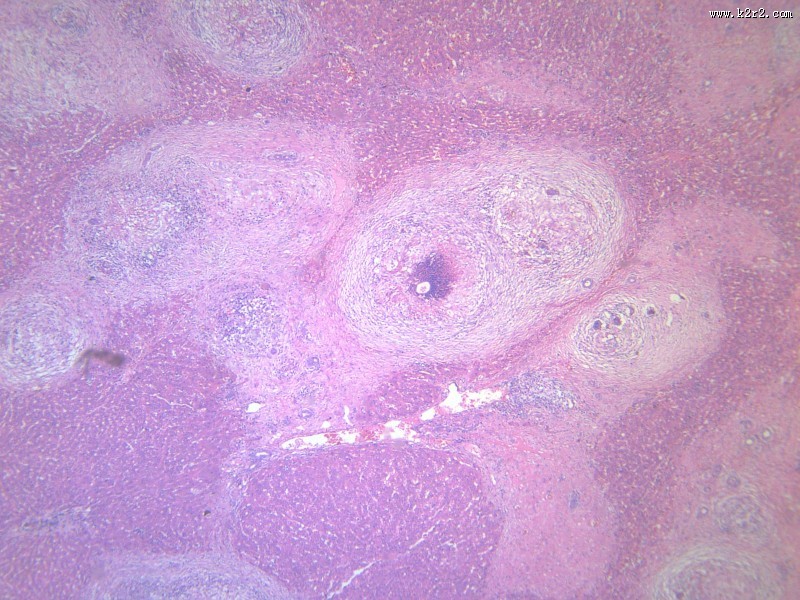

虫卵肉芽肿 - 第5张

第 5 / 12 张